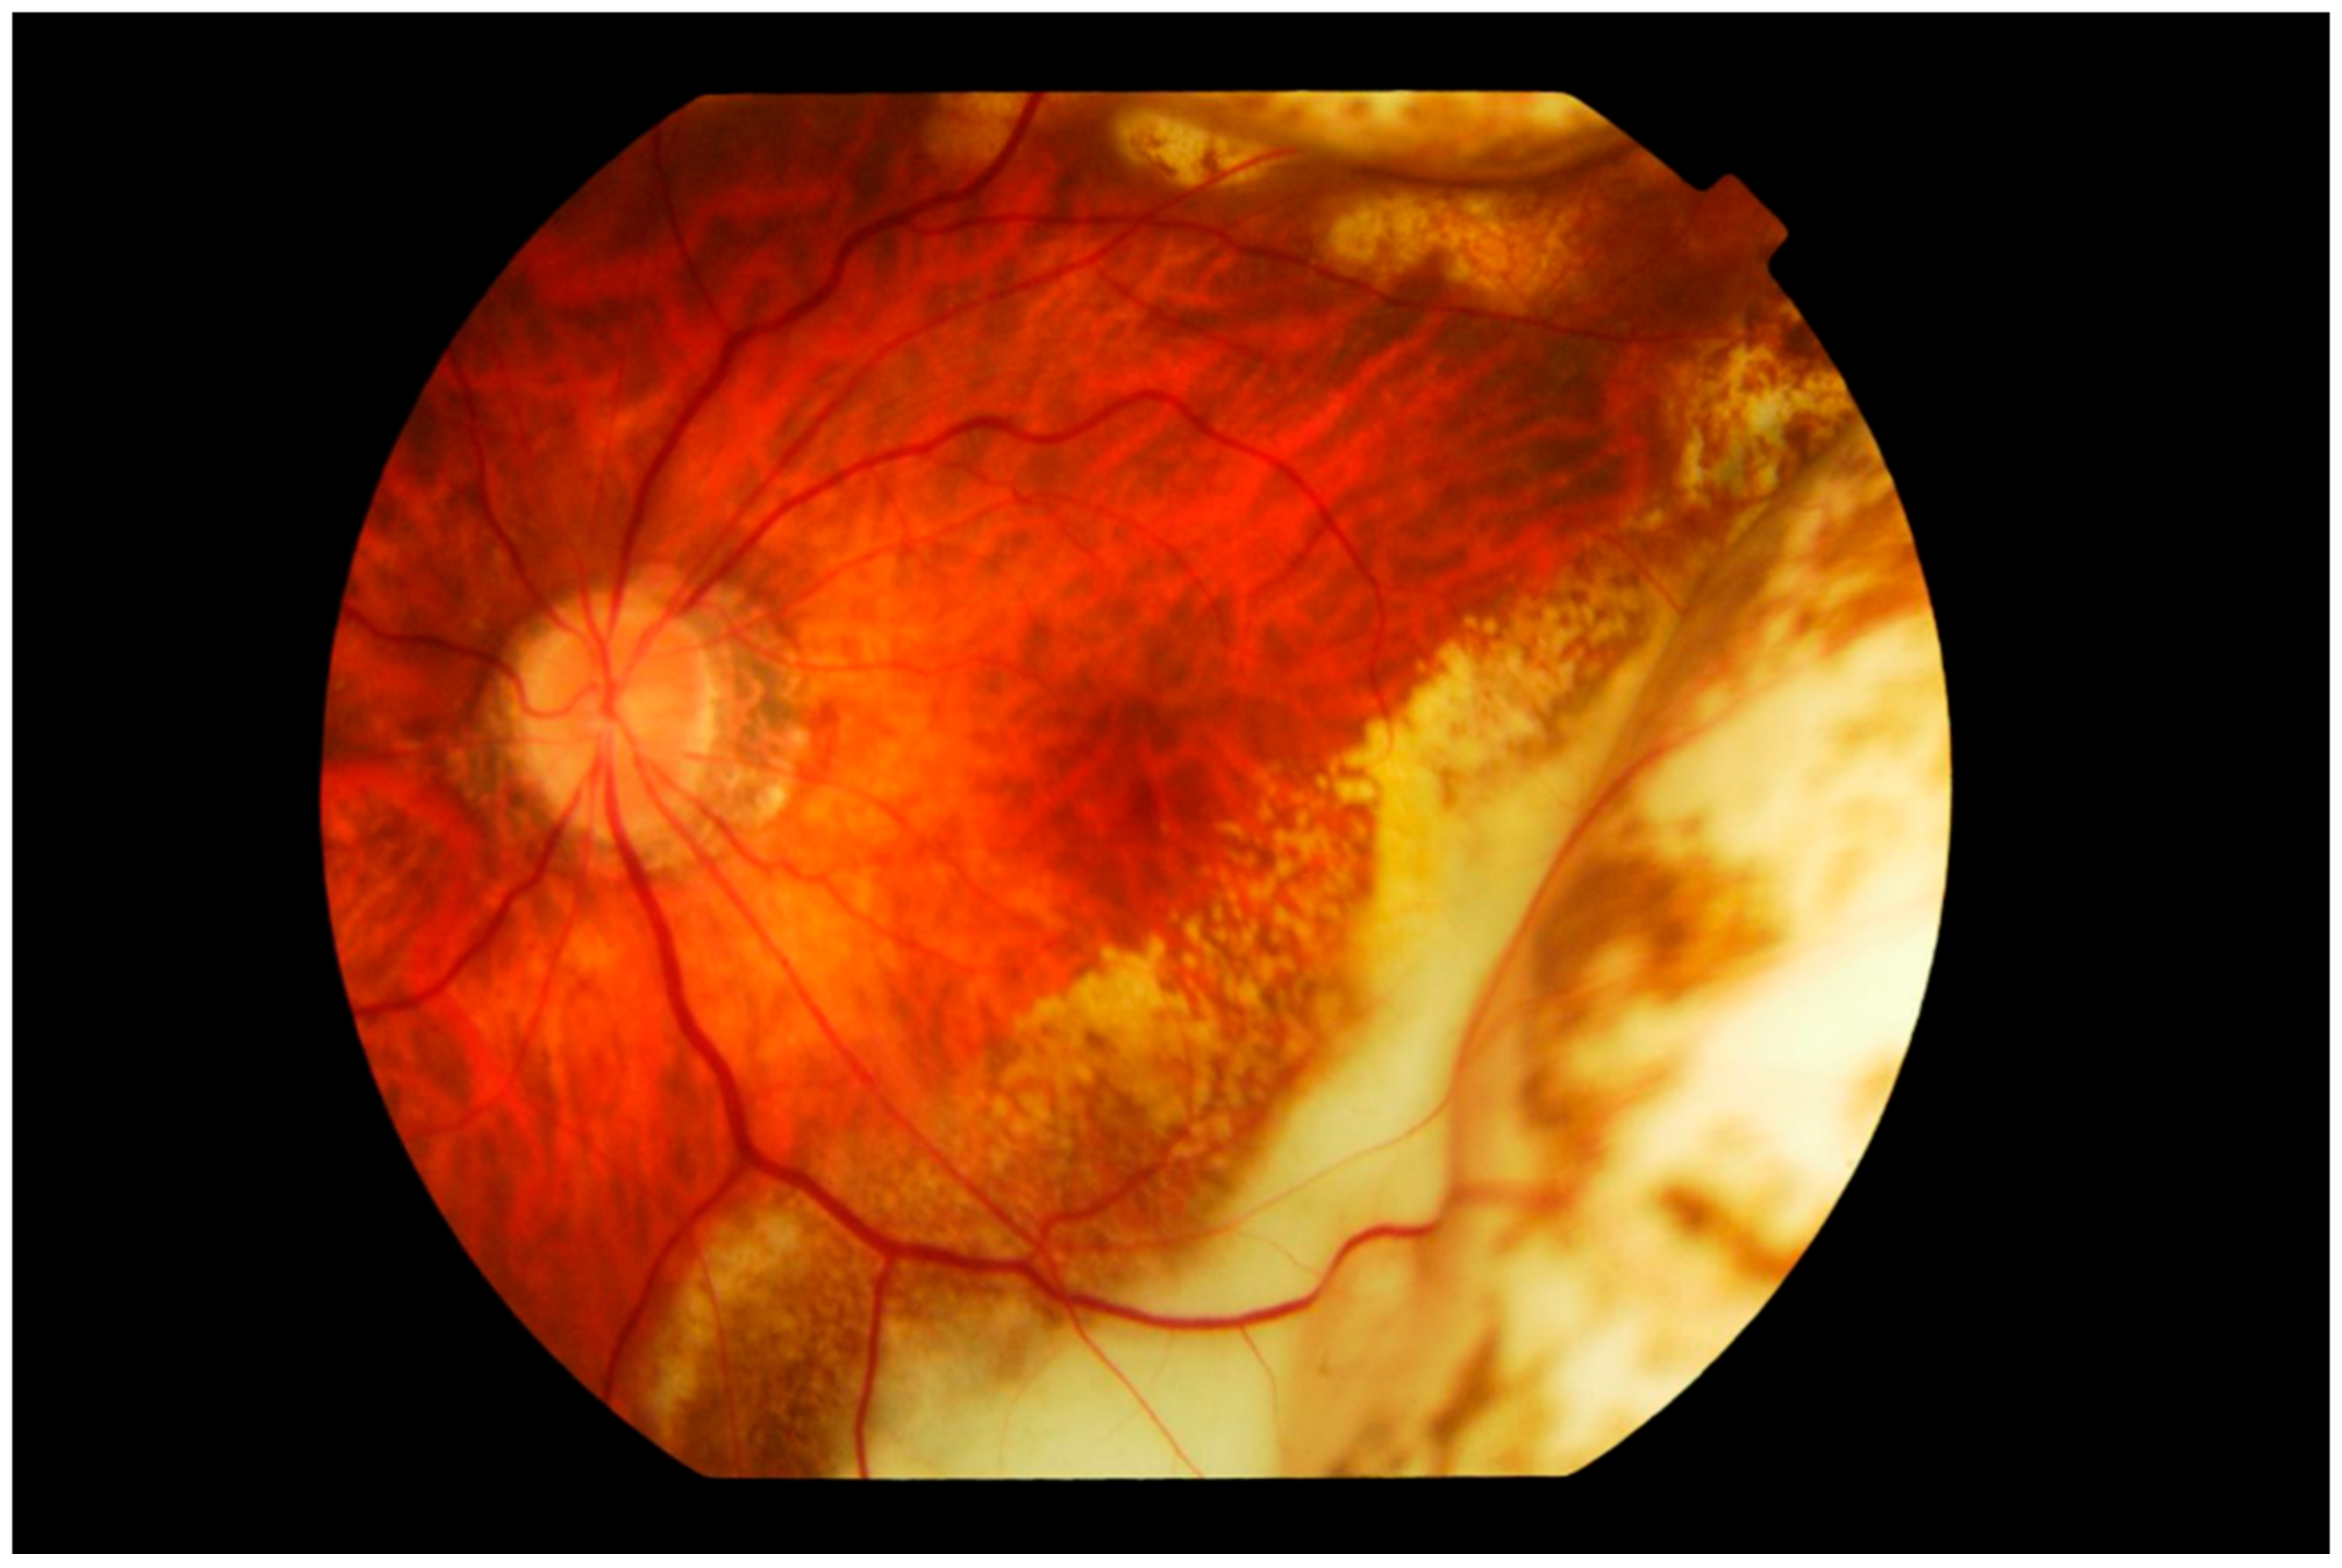

3. Clinical Features

Differential Diagnosis